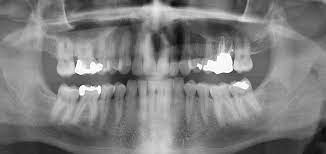

Orthopantomogram (OPG) dental imaging offers a panoramic, two-dimensional view of the mouth. This advanced technology captures an image of the entire dental structure in one go, including teeth, jaws, and surrounding bones. It's like having a complete map of the mouth, allowing dentists to accurately diagnose issues that were previously hidden.

When Anjali took Aryan for an OPG scan, the results were immediate and illuminating. The scan revealed an impacted wisdom tooth, which had been causing the pain. With this clear diagnosis, the dentist could develop a precise treatment plan, alleviating Aryan’s discomfort quickly and effectively.